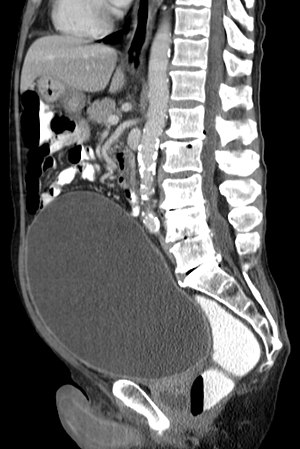

Urinary retention with greatly enlarged bladder as seen by CT scan.

Analysis of urine flow may aid in establishing the type of micturition (urination) abnormality. Common findings, determined by ultrasound of the bladder, include a slow rate of flow, intermittent flow, and a large amount of urine retained in the bladder after urination. A normal test result should be 20-25 mL/s peak flow rate. A post-void residual urine greater than 50 ml is a significant amount of urine and increases the potential for recurring urinary tract infections. In adults older than 60 years, 50-100 ml of residual urine may remain after each voiding because of the decreased contractility of the detrusor muscle.[4] In chronic retention, ultrasound of the bladder may show massive increase in bladder capacity (normal capacity is 400-600 ml).